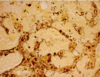

What infectious cause of hepatitis can be observed with this staining?

leptospirosis